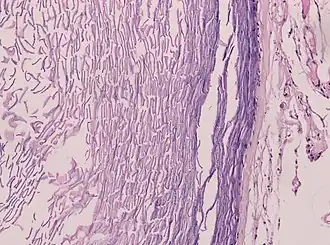

An epidermoid cyst or epidermal inclusion cyst[1] is a benign cyst usually found on the skin. The cyst develops out of ectodermal tissue. Histologically, it is made of a thin layer of squamous epithelium.

Epidermoid cysts are usually diagnosed when a person notices a bump on their skin and seeks medical attention. The definitive diagnosis is made after excision by a pathologist based on microscopic appearance of a cystic lesion lined by cornified epithelium containing lamellated keratin without calcifications. They can also be seen as isointense lesions on MRI or hyperintensities on FLAIR.